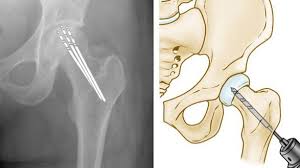

2. تصویربرداری رادیولوژی: عکس X-ray می تواند تغییرات استخوانی را در مراحل پیشرفته نشان دهد.

3. ام آر آی (MRI): حساس ترین روش برای تشخیص زودهنگام نکروز استخوان و شناسایی بافت آسیب دیده.

4. سی تی اسکن (CT Scan): برای بررسی دقیق ساختار استخوان و اندازه گیری عمق آسیب استفاده می شود.

۳. تعویض مفصل لگن

در مراحل پیشرفته، زمانی که استخوان و مفصل دچار تخریب شدید شده باشند، تنها راه درمان، تعویض مفصل لگن است. این جراحی باعث کاهش درد، بازگرداندن حرکت و بهبود کیفیت زندگی بیمار می شود. تجربه و مهارت جراح متخصص مانند دکتر مهرداد منصوری نقش حیاتی در موفقیت این جراحی دارد.